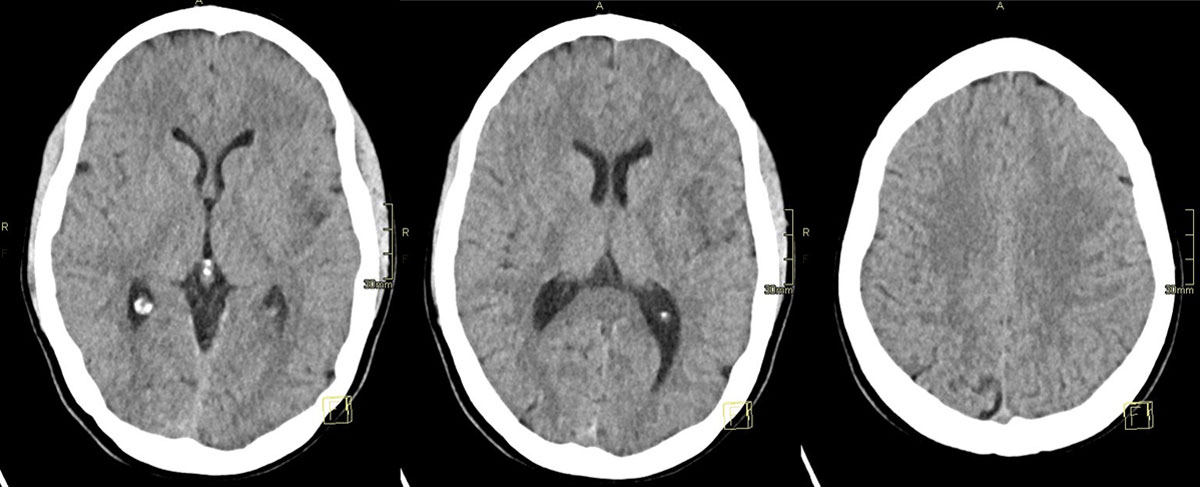

CT – CTA - CTP

24h CT-scan

24h CTA and CTP